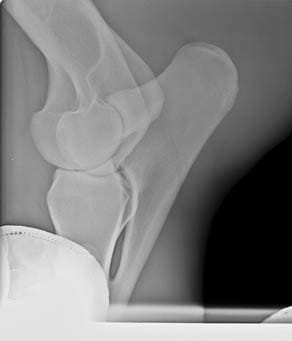

La radiología digital directa es una herramienta indispensable para el estudio v valoración en numerosas áreas de la atención veterinaria: valoración de cojeras, exámenes pre-compra, estudios radiológicos, diagnósticos más precisos en patologías, heridas, enfermedad…

Por eso nos mantenemos al día y nos renovamos con nuevos equipos de radiología digital directa que incorporan herramientas de diagnóstico y valoración con ventajas como:

- Herramientas de medidas más completas y potentes

- Medidas e imagen 3D para evaluación del pie equino

- Imagen hibrida. Diagnóstico v herrado